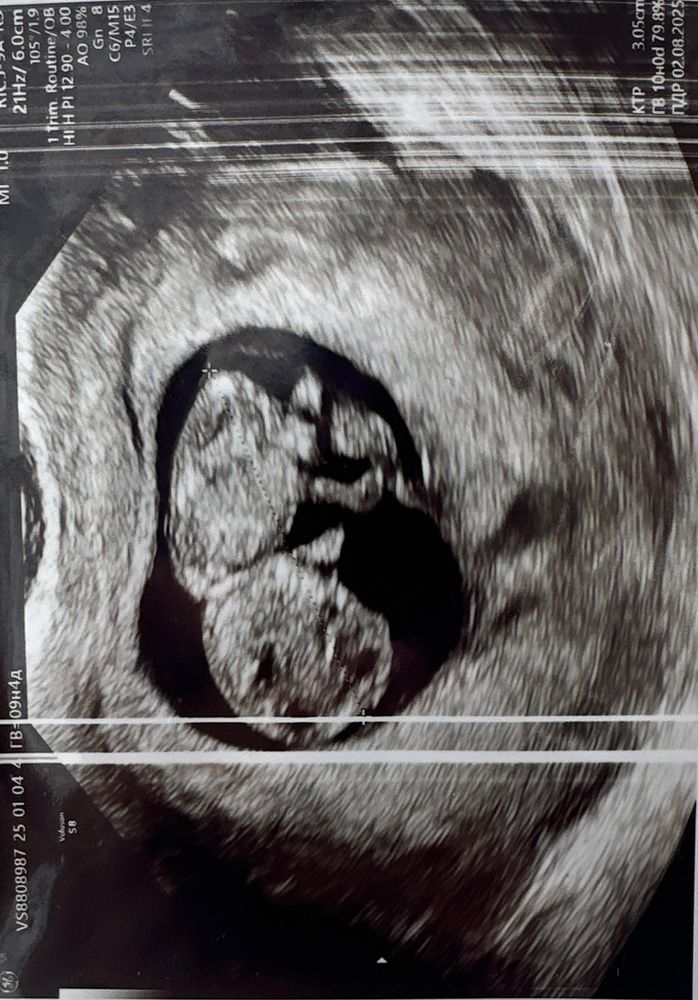

Ждун, я не придавала значения. Вчера скрин был первый, в дневнике фото есть. Там тоже впритык

А вот в 12 + недель на скрининге уже заполнил все место. Изображение

Размер пя в 9,4 недель не измеряли. Но я не волновалась, места ему хватало с виду. Изображение

У вас на картинке ок выглядит. Я так скажу: в эту беременность на УЗИ бегала часто. И меряют ПЯ кто во что горазд. Было, что на неделю позже пя как будто уменьшилось (спойлер: нет). Очень желаю, чтобы все у вас было отлично!

Екатерина, это я мерила у одного и того же узиста🥲 Спасибо большое🙏🏻 Только картинка меня немного успокаивает, но соотношение размеров…